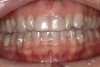

“Masking buildup” was performed (Figure 9), according to the concepts of immediate dentin sealing.14 A slightly opaque veneer composite cement was used for cementation and to enhance the masking effect (Figure 10).

Fig 9. Final veneer preparations after masking with flowable composite.

Figure 9

Fig 10. Final smile.

Figure 10